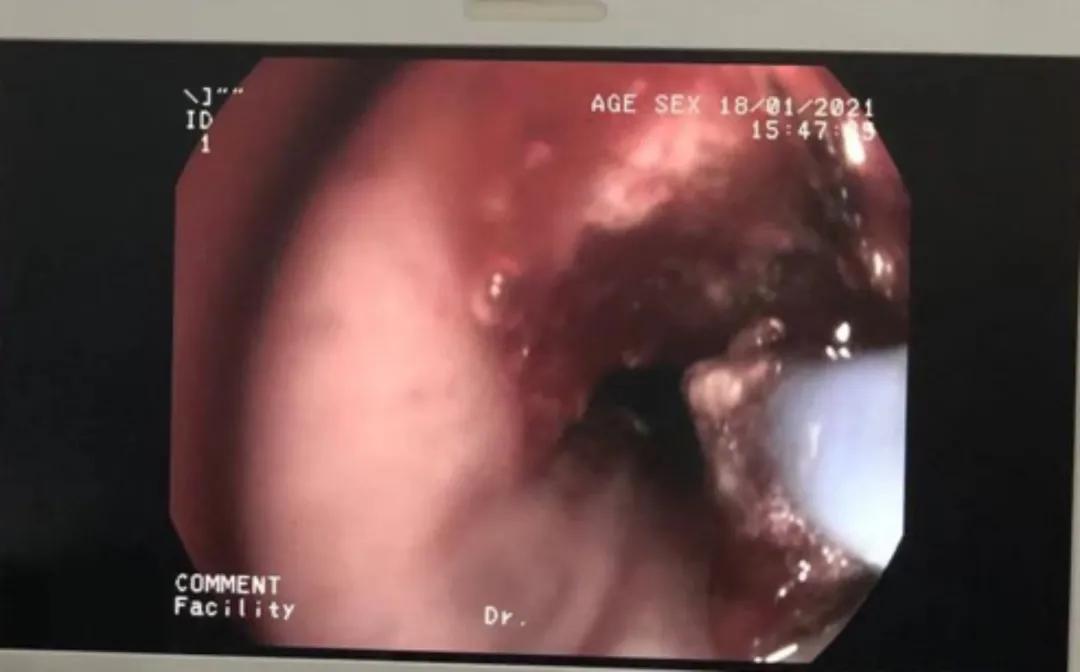

在专家的现场指导下,吴西雅顺利地将硬镜插入右肺中叶。接下来的操作因为有了硬镜鞘管的气道保护和操作孔道,软镜和冷热消融操作较稳妥。1小时后,李先生右肺下叶支气管顺利打通。术毕患者约50分钟后清醒,气促情况明显缓解,状态良好,未感特殊不适。

冷冻仪冻取、冻溶打通管腔

氩气刀对肿瘤组织进行热消融

操作前(左)后(右)照片对比